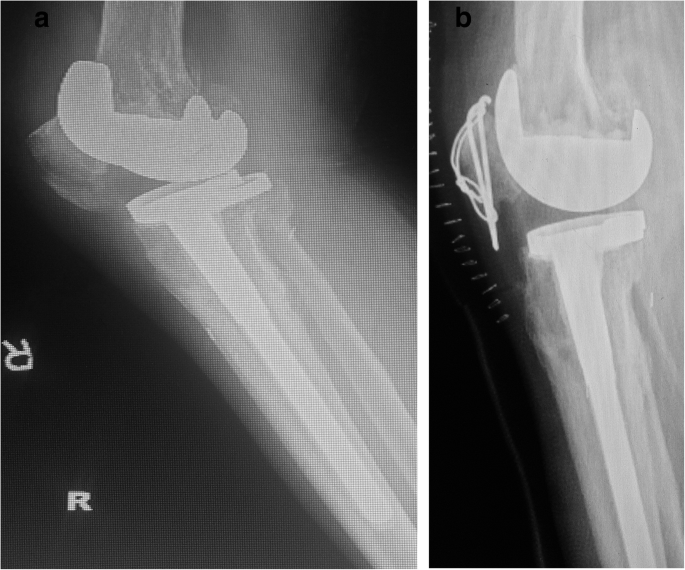

There was no reoperation. None of the patients developed infection, deep vein thrombosis, or pulmonary embolism. The mean follow-up period lasted 16 months (range: 12–20 months) (Table 1). The average arc of motion was 110° (range: 80°–130°). The functional knee score was 77 (range: 70–87). The mean Knee Society score was 84 (range: 75–89) (Table 2). The findings of pre- and postoperative X-ray examination of implants are presented in Figs. 1, 2, 3, 4.

A 72-year-old women who suffered a PPPF (case 3 in Table 1). a Preoperative lateral view showing a posterior stabilized system (Depuy) with stem extender. b The displaced inferior pole fracture is fixed with tension band wiring